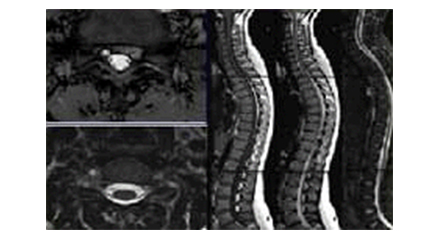

• 척추 자기 공명 영상(Spine Image) 이미지

척추 자기 공명 영상

(Spine Image)

기존의 장비보다 우수한 선명도를 제공함으로서 척추 쪽에 발생하는 추간판 탈출증 및 진단에 있어서 매우 탁월한 영상을 제공합니다.